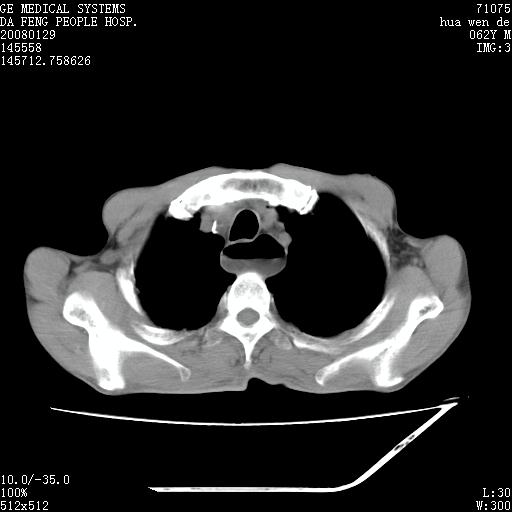

男性,67岁。作肺部检查时发现

考虑:胸腔胃并支气管瘘(并发肺炎,肺脓肿形成)。

理由:1、右上肺内病灶,空洞形成,有液平。

2、肺内多处炎症。

1.整个食管扩张,未见明显占位性病变,贲门区亦未见明显占位病变,考虑:贲门失驰缓症;

2.右上肺病变边缘可见毛刺,囊壁厚度不均匀,周围境界较清楚,未见炎性渗出性影,右上肺外带可见片状影,边缘不清,考虑:肺癌伴空洞形成、右上肺炎。

食管全程扩张,壁均匀不厚,喷门失弛缓症

右上肺空洞可见液平,临近肺野磨玻璃密度,考虑1.结核2.脓肿

贲门失驰缓症.肺部感染伴脓肿形成。支持!是否吸入性要结合临床诊断,我们影像是看不出来的。但胸腔胃能排除(1.没有手术史支持,2.双侧胸廓对称,胸壁、肋骨及胸膜规整,3,食管壁明显扩张内壁光滑,胸腔胃黏膜皱襞多较厚)。